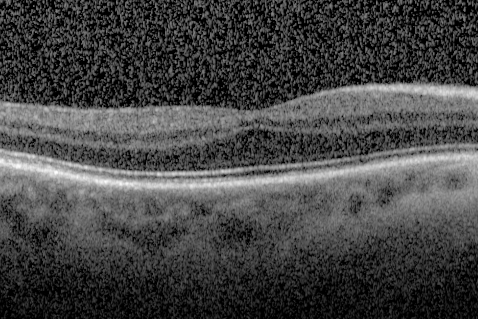

Foveal hypoplasia - aplasia

SD OCT shows persistent plexiform layers in the center of the macula